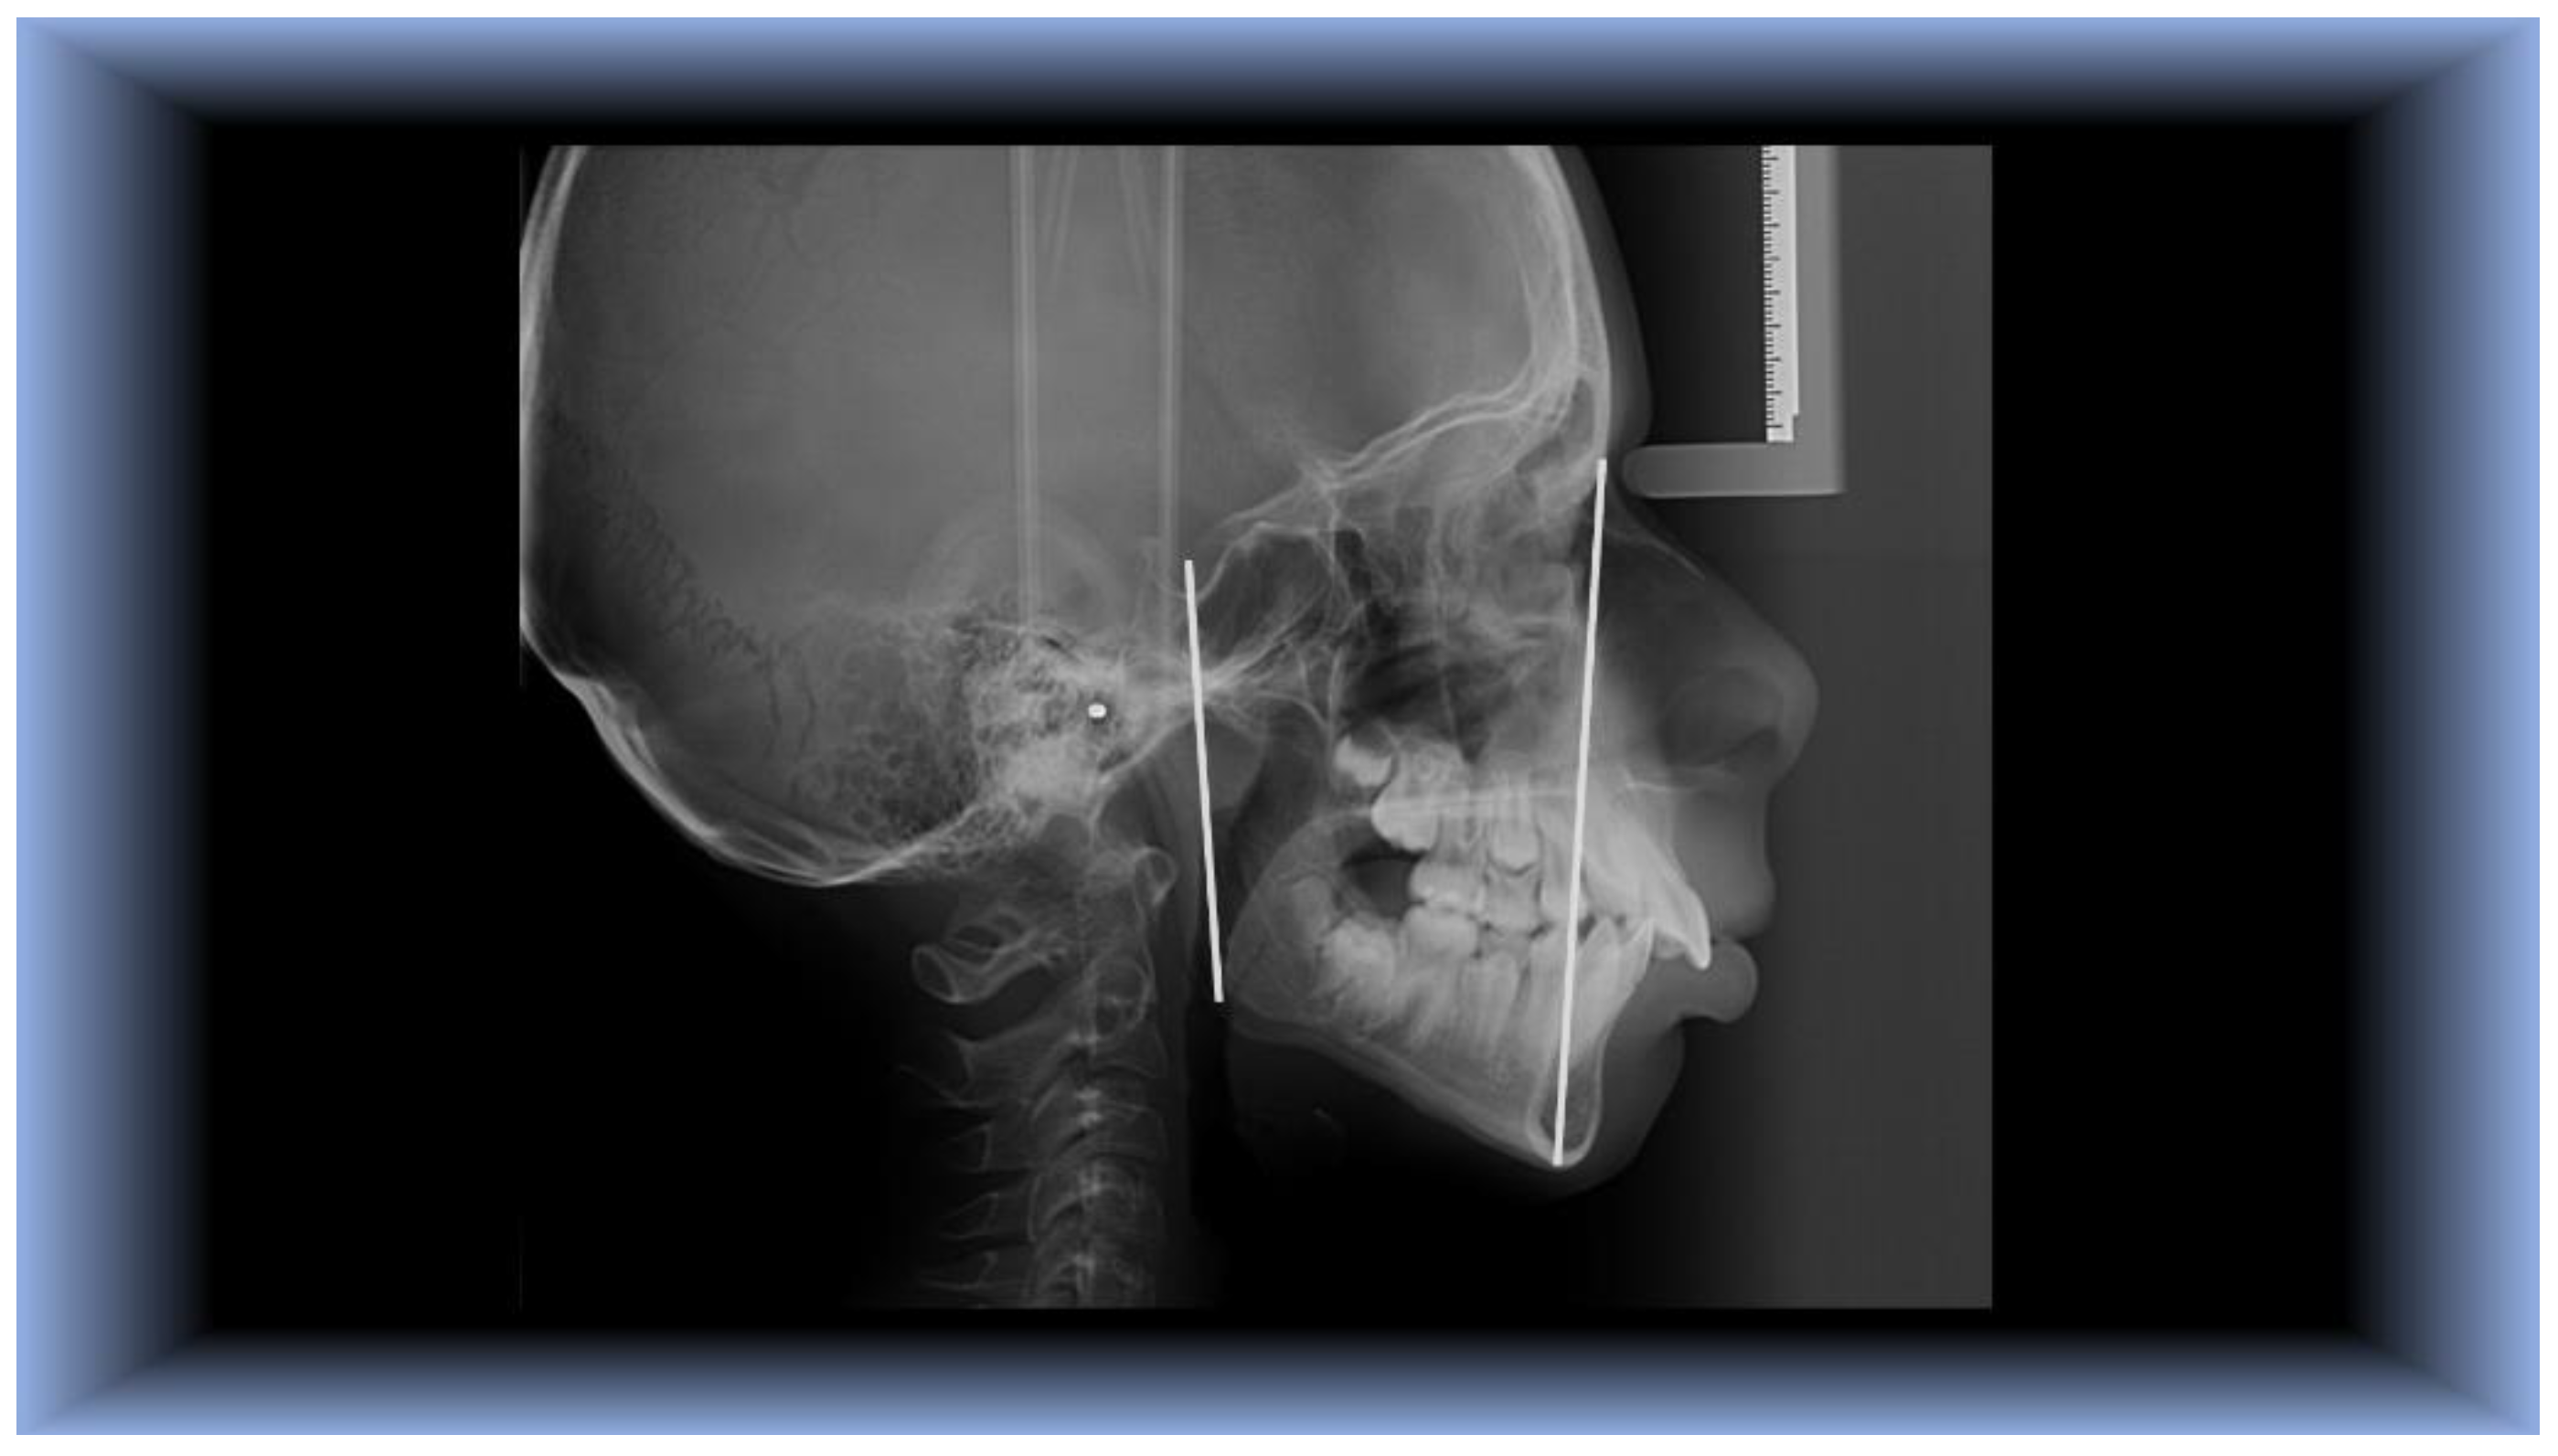

The cephalometric landmarks and planes used in this experiment were as follows (Figure 1):

Landmarks:

• S- Sella turcica– mid-point of the hypophyseal fossa.

• N- Nasion -most anterior point on the Naso-Frontal suture in the medial plane.

• Go- Gonion - meeting point of posterior ramal plane and the MP angle.

• Me- Menton - the lowest point in the median plane of the chin.

Planes that have been built include the following:

• N-Me (Nasion-Menton) line

• S-Go (Sella-Gonion) line.

Figure 1. Constructed planes and cephalometric markers were used in this investigation, Nasion-Menton and Sella-Gonion.